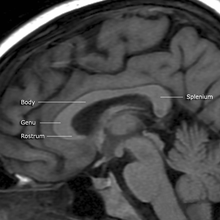

The posterior (back) portion of the corpus callosum is called the splenium; the anterior (front) is called the genu (or "knee"); between the two is the truncus, or "body", of the corpus callosum. The part between the body and the splenium is often markedly narrowed and thus referred to as the "isthmus". The rostrum is the part of the corpus callosum that projects posteriorly and inferiorly from the anteriormost genu, as can be seen on the sagittal image of the brain displayed on the right. The rostrum is so named for its resemblance to a bird's beak.

Corpus callosum parts on MRI